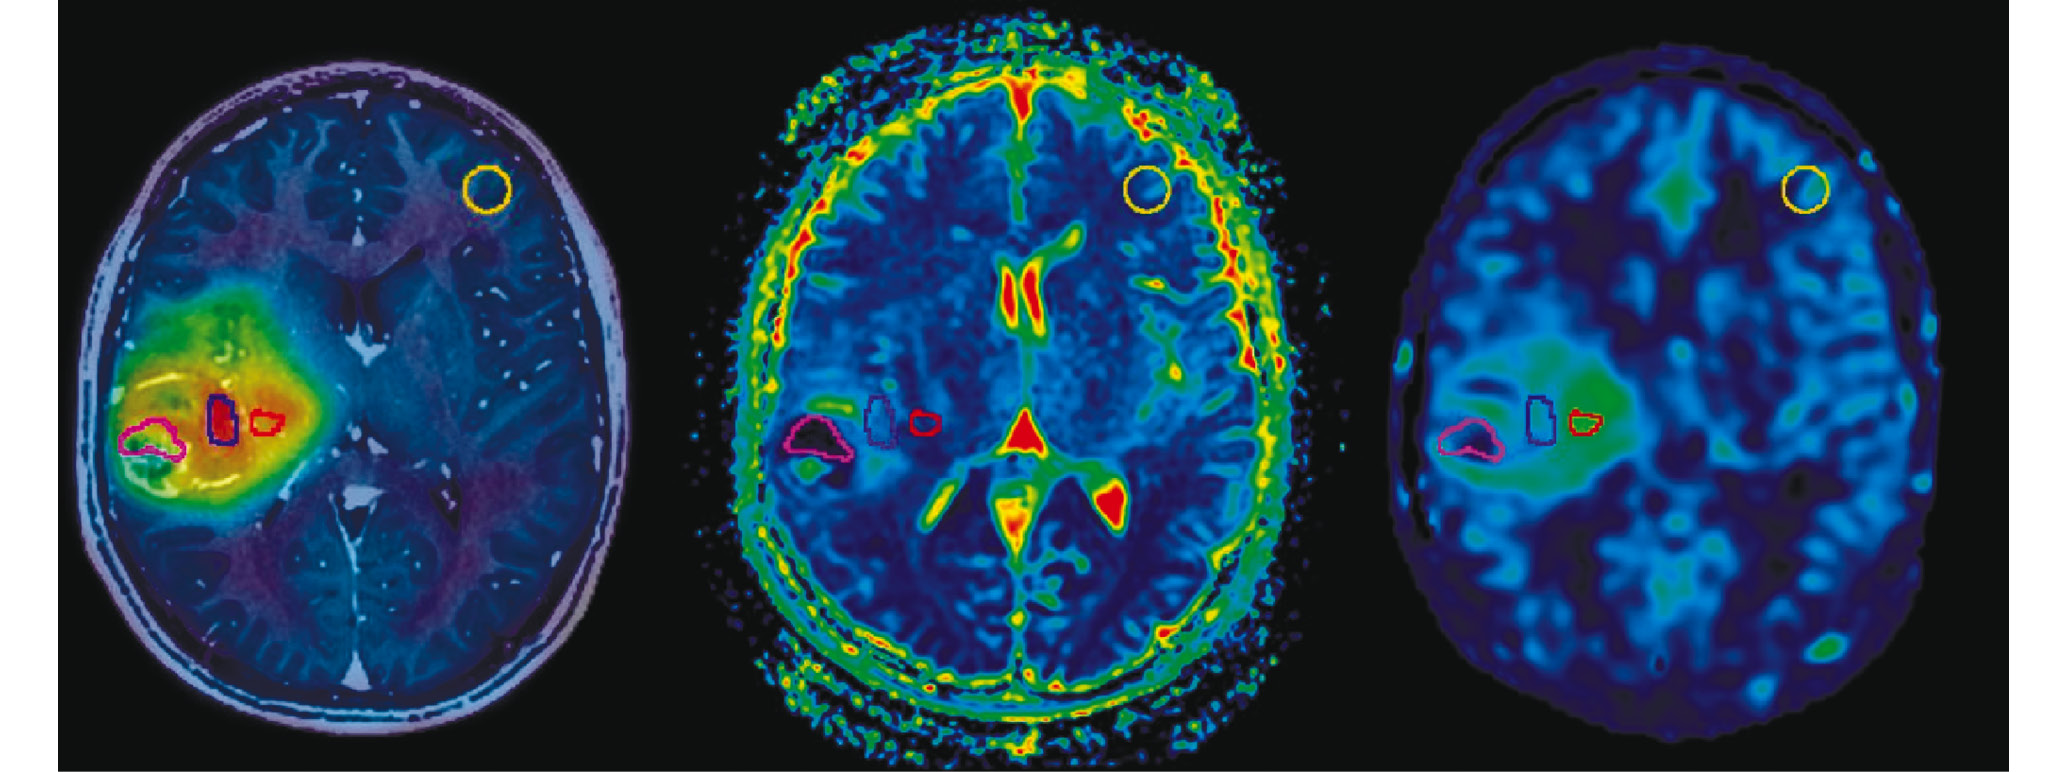

Зоны интереса (Volume of Interest – VOI) на МРТ и ПЭТ-сканах выбирались в соответствии с принятым протоколом обработки данных в объеме 1см3 (рис. 1): 1) VOI наибольшей метаболической активности МЕТ на карте его распределения (МЕТmax); 2) VOI минимальных значений измеряемого коэффициента диффузии на карте ИКД (ADCmin); 3) VOI максимальных значений скорости кровотока на карте ASL-перфузии (CBFmax).

Рис. 1. Глиобластома правого полушария головного мозга. Зоны интереса на ПЭТ и МРТ изображениях: 1) карта распределения метионина (МЕТ), совмещенная с T1ВИ после контрастрирования; 2) карта измеряемого коэффициента диффузии (ADC); 3) карта объемного мозгового кровотока (CBF) ASL перфузии. Цветом обозначены зоны интереса (VOI) сопоставленные друг с другом: синий – максимальное накопление метионина (METmax), розовый – минимальные значения измеряемого коэффициента диффузии (ADCmin), красный – максимальные значения кровотока (CBFmax), желтый – измерения в нормальной паренхиме мозга. В данном клиническом примере зоны интереса не пересекаются.

Fig. 1. Right hemisphere glioblastoma. PET and MRI areas of interest: 1) methionine distribution map (MET) combined with contrast enhancement T1W; 2) apparent diffusion coefficient map (ADC); 3) ASL cerebral blood flow map (CBF). Mapping areas of interest (ROI) to each other is indicated by color: blue – methionine maximum accumulation (METmax), pink – diffusion coefficient minimum (ADCmin), red – cerebral blood flow maximum (CBFmax), yellow – normal brain parenchyma measurement. In this clinical case VOI didn’t match.

Далее все вышеперечисленные контуры VOI с помощью программного обеспечения автоматически переносились на другие карты и сопоставлялись друг с другом – рис. 1 и 2.